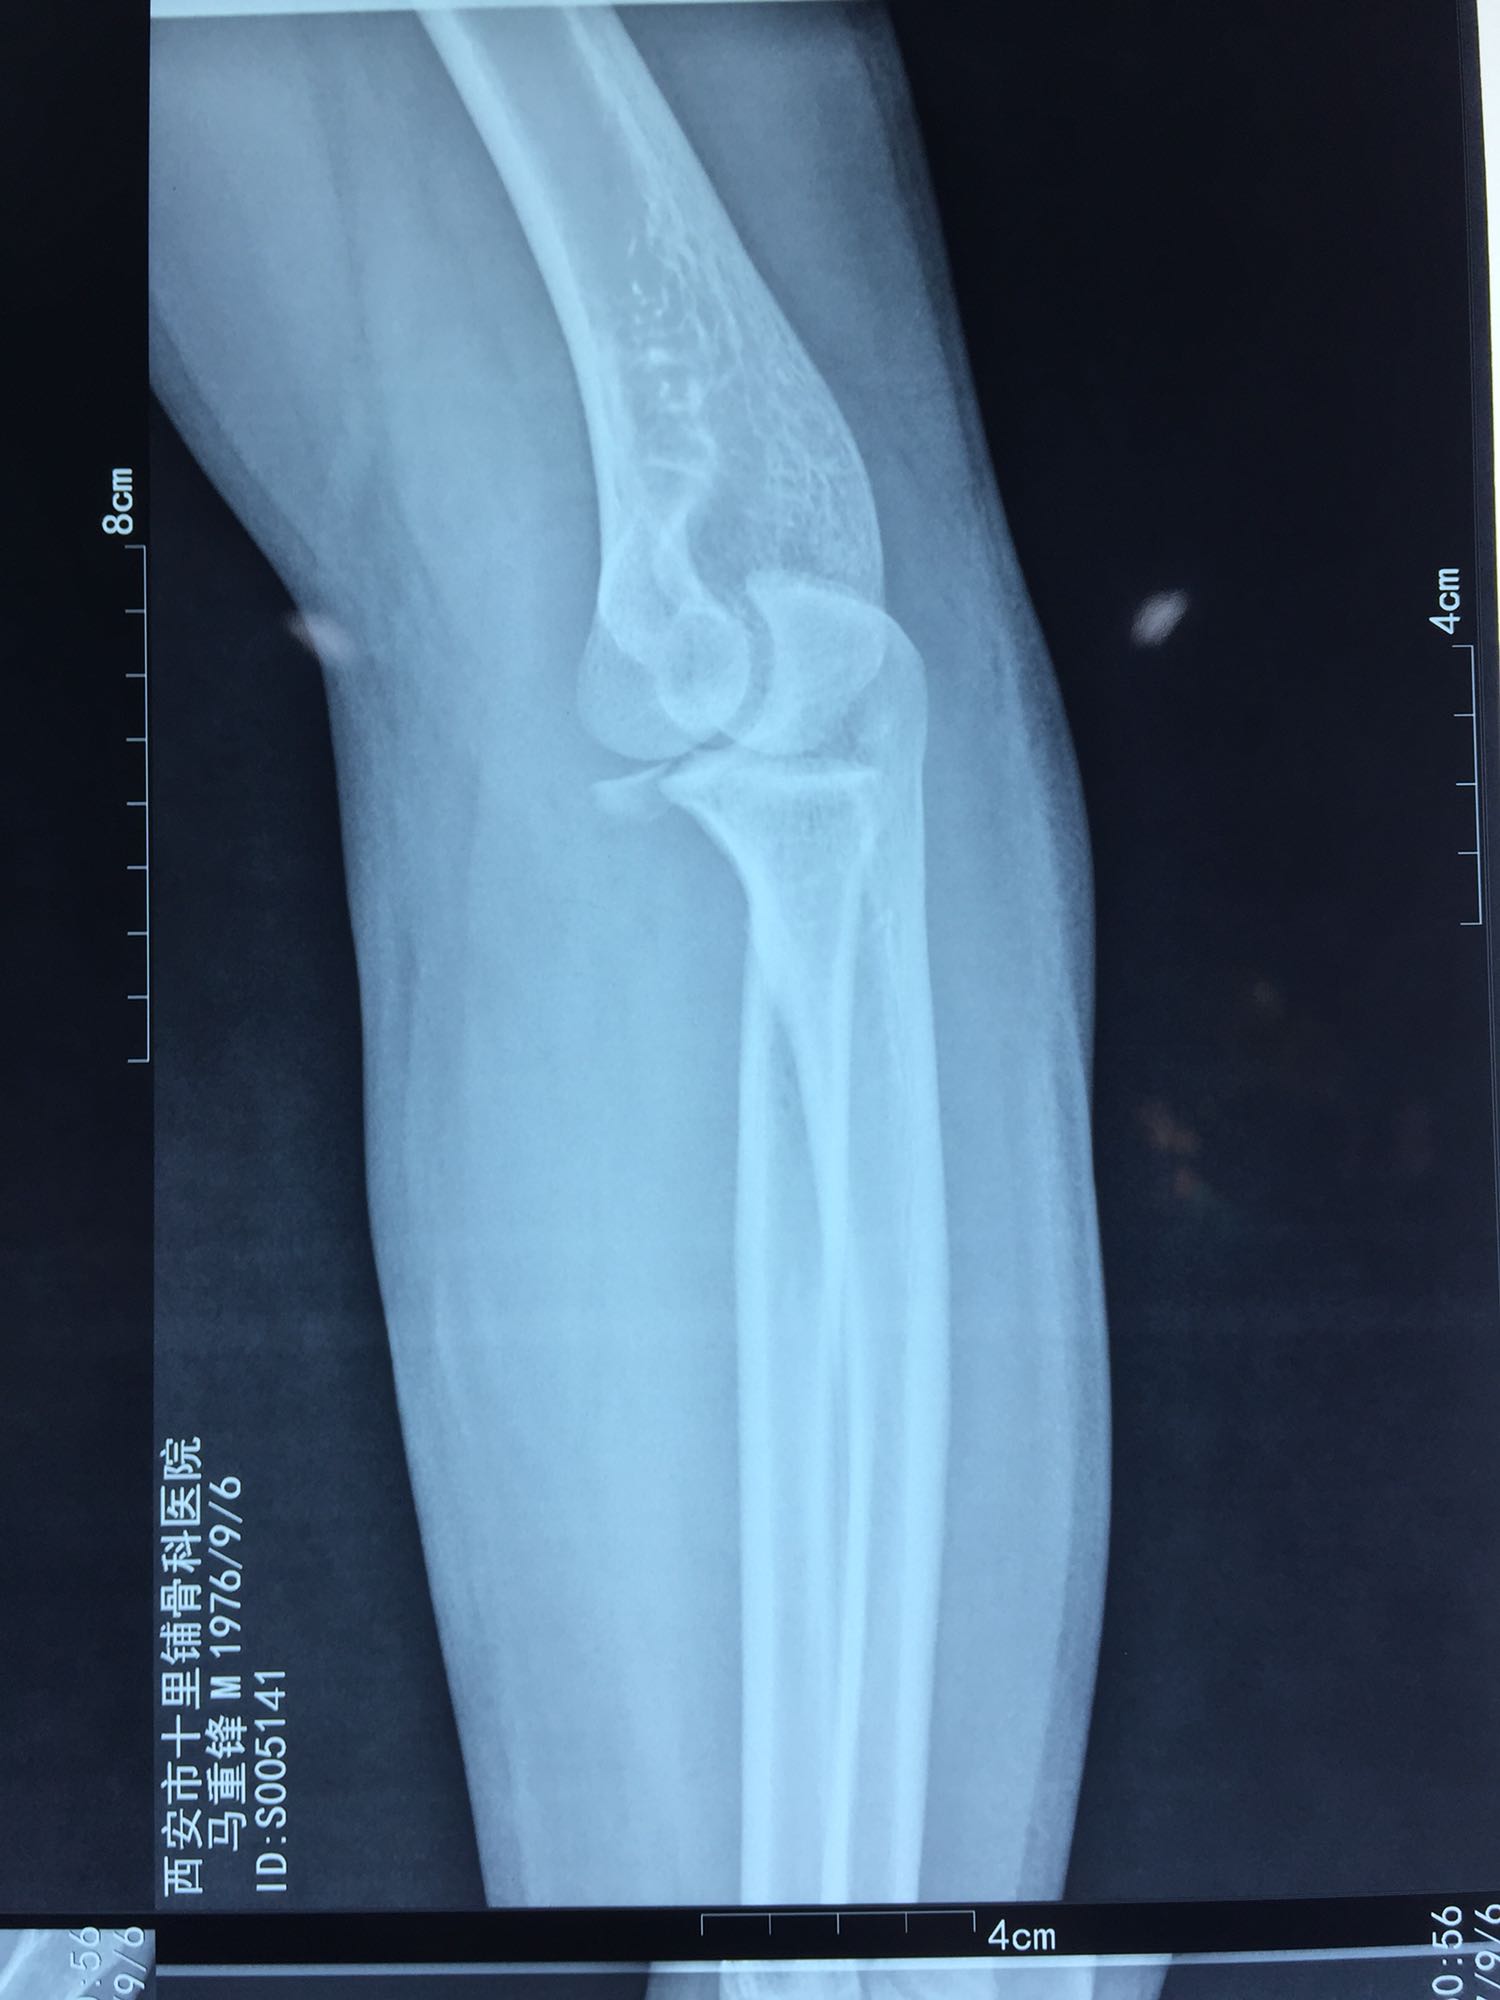

左肘关节高度肿胀,压痛强阳性,肘关节明显活动受限,末梢血运良好,各指关节运动正常。 X线片及CT如图:

1、左尺骨冠状突骨折;2、左肱骨外髁撕脱骨折 治疗:入院后伤肢石膏外固定,给予局部冷敷消肿治疗,于伤后一周行骨折手术治疗,先行前内侧切口复位固定冠状突骨折,活动肘关节发现关节明显不稳定,随取外侧切口,复位固定肱骨外髁,修补外侧副韧带,肘关节明显稳定。术中术后片子如下